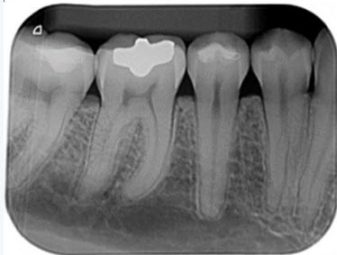

coronales

Es una pequeña radiografía que en este caso usamos para valorar solo las coronas de los dientes. Se hace morder un posicionador y de esa manera salen hasta 4 o 5 coronas superiores e inferiores. Esto nos permite detectar caries. Principalmente interproximales.